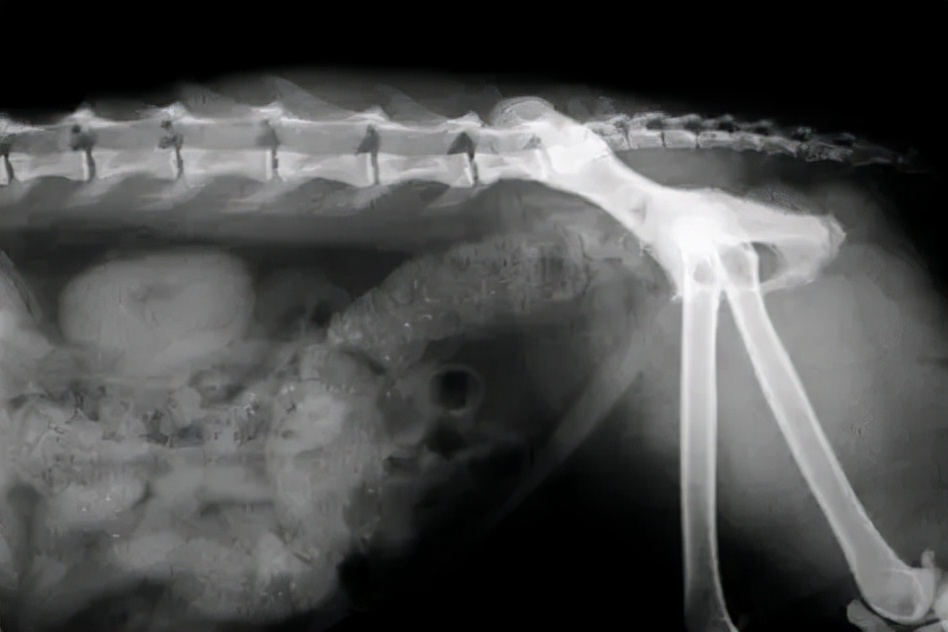

便秘X线片